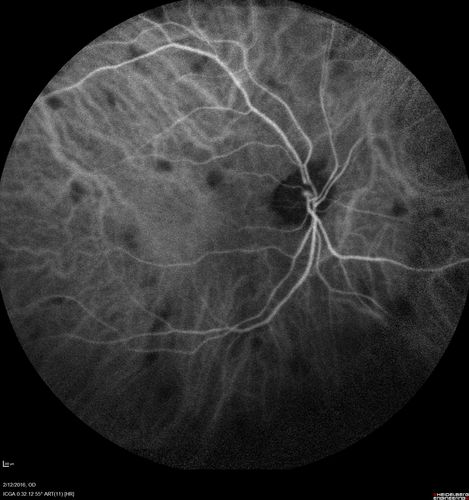

Sarcoidosis Multifocal Choroiditis

66 year old man with dense cataracts and recurrent uveitis. Images show multifocal choroidal granulomas from sarcoidosis more in the right eye than the left eye.